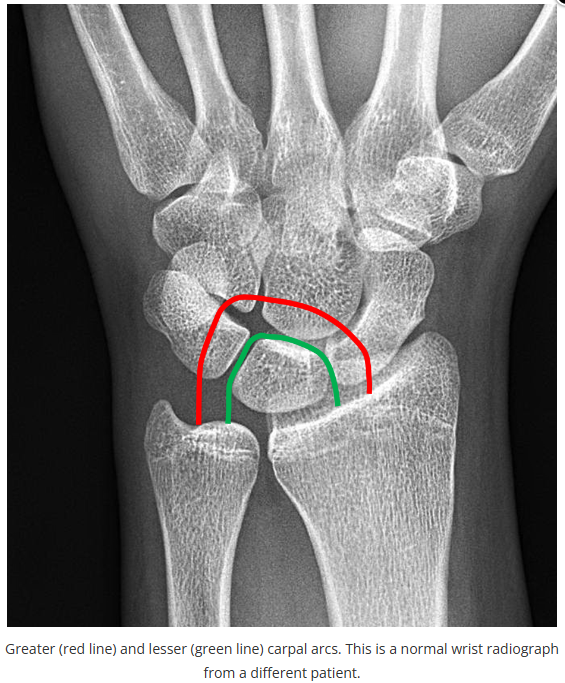

这些腕与手的骨折X线片如果没有标注箭头,你还能识别出来吗?

X线读片是骨科医生的基本功。

今天是腕部与手的X线片。所有X线片都

带有标注和说明

,可以选择长按图片,

自动翻译相关说明

。